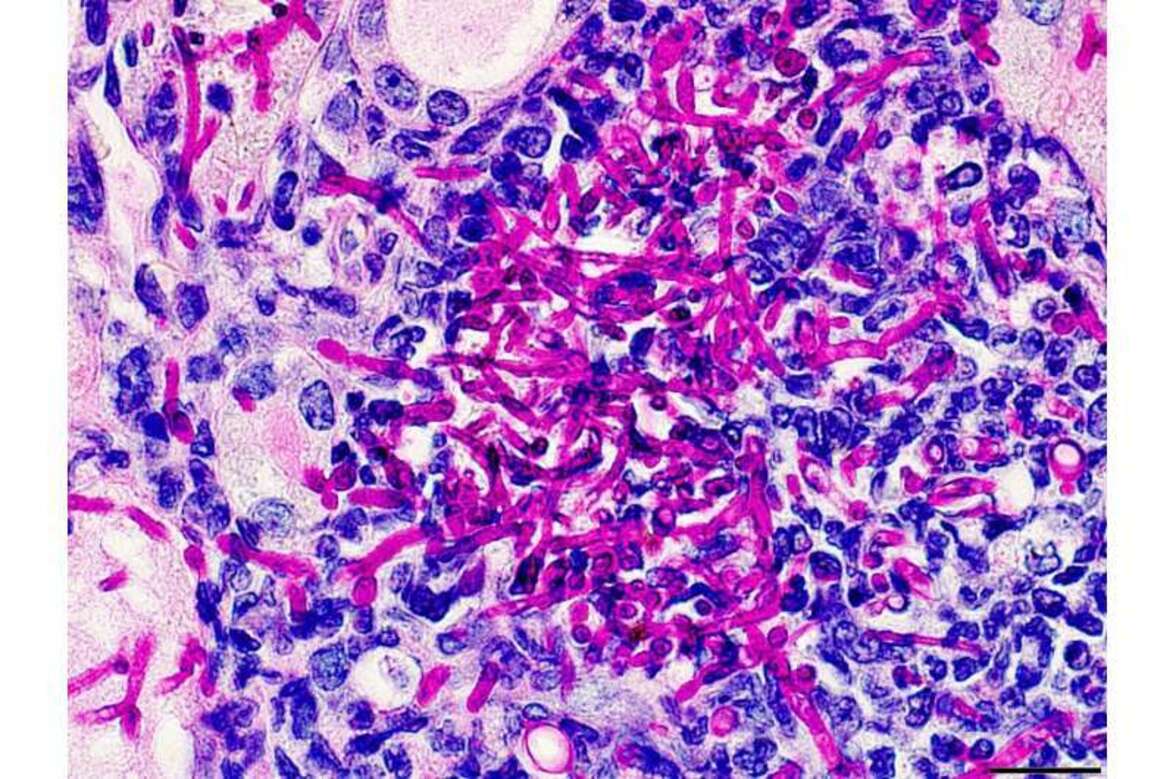

Грибок Candida albicans вызывает инфекции, которые могут проявляться как поверхностно на коже и ногтях, так и проникать в органы и кровоток. В последние десятилетия распространенность системного кандидоза возросла из-за увеличения числа пациентов с ослабленным иммунитетом в результате болезни или лечения, длительного приема антибиотиков и некоторых заболеваний, таких как заболевания почек. Лечение системного кандидоза стало более трудным из-за устойчивости к противогрибковым препаратам, ограниченных средств ранней диагностики и отсутствия одобренных противогрибковых вакцин. По мнению Парты Бисвас, ведущего автора статьи из Университета Стоуни Брук (США), эти проблемы стали препятствиями на пути лечения системного кандидоза и иллюстрируют необходимость в новых терапевтических стратегиях.

Бисвас и его коллеги использовали мышиную модель кандидоза для изучения нейтрофилов, которые являются основными эффекторными клетками, ответственными за быстрое уничтожение грибков при кандидозе. Однако эта естественная противогрибковая активность в значительной степени зависит от внеклеточной глюкозы, которой становится недостаточно при этом инфекционном процессе, поскольку C. albicans конкурирует за питательные вещества. Обычно метаболическая конкуренция внутри организма-хозяина представляет собой враждебную среду, которая ограничивает выживание и функционирование нейтрофилов, особенно при наличии сопутствующих метаболических нарушений (заболеваний).